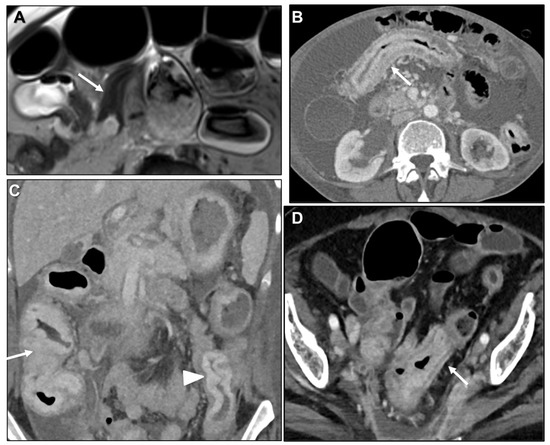

Malignant Target Sign

Homogeneous Delayed Enhancement

Concentric Ring Pattern

Length